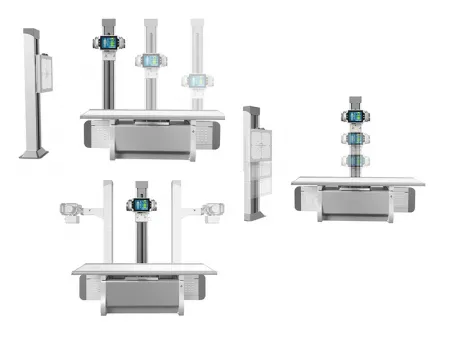

Equipo de Rayos X Fijado al Suelo, SHO-DDX03

Este sistema radiográfico de doble columna está diseñado especialmente para salas DR, ofreciendo una estructura robusta y versátil que facilita el posicionamiento en distintos ángulos y alturas. Es ideal para realizar estudios detallados de cráneo, tórax, abdomen, columna lumbar y extremidades, y permite trabajar con proyecciones PA, laterales y otras imágenes clínicas estáticas con alto nivel de precisión.

| Movimiento del soporte de columna | |

| Soporte para tubos | |

| Movimiento arriba-abajo | 28-128 cm |

| Movimiento izquierda-derecha | 78.5-157 cm |

| Ángulos de rotación del soporte | 180° a -180° |

| Ángulos de rotación del tubo | ±90° |

| Soporte de Bucky | |

| Movimiento ascendente-descendente del casete FPD | 4-175 cm |

Diseñado para moverse con fluidez y precisión, este sistema garantiza una captura de imágenes eficiente y sin contratiempos. - Columna y tubos rotatorios:

Gracias a su capacidad de rotación, el equipo se adapta fácilmente a diferentes posiciones, brindando mayor flexibilidad para ajustarse a cada examen radiológico.